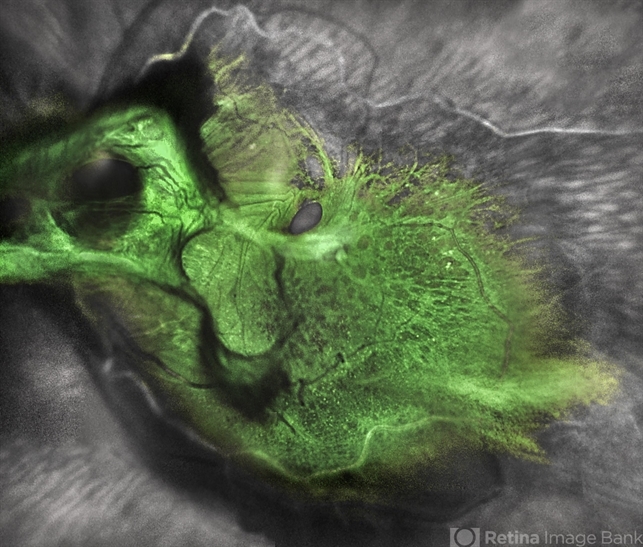

- tractional retinal detachment, macular hole, Multispectral imaging

- Multicolor fundus photo taken on the Spectralis OCT2 (Heidelberg Engineering GmbH).

- Tractional retinal detachment with macular hole in a 76-year-old female.